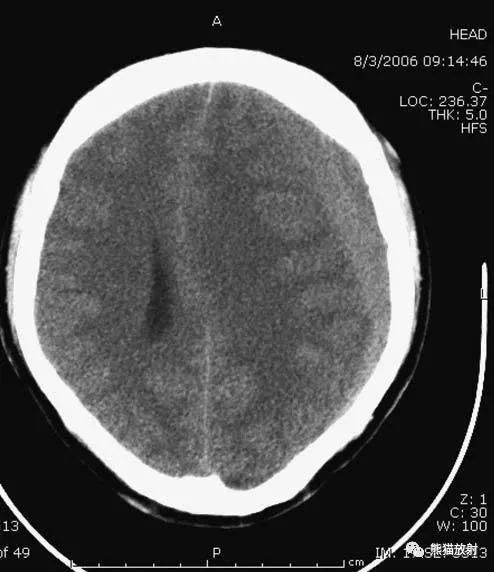

6、脑梗死

缺血性脑卒中早期:脑水肿,灰白质分界模糊,脑沟消失;

中期:病变区域密度减低;

晚期:脑实质体积缩小。

A:陈旧性脑梗死,右枕叶体积缩小;

B:左枕叶急性脑梗死,灰白质分界模糊,脑沟消失;

另一患者:

C、D:亚急性期脑梗死,低密度,无明显占位效应。

▲左侧大脑中动脉供血区脑梗死(亚急性期):

低密度,轻度水肿。

缺血性脑卒中发作2-4天时,占位效应最明显。